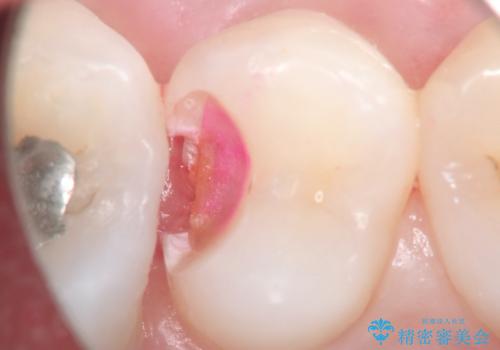

- 定期検診にて虫歯を発見したため、セラミッククラウン、セラミックインレーにて治療を行いました。

小臼歯の虫歯は歯髄に近かったため、部分的断髄法にて歯髄を部分的に保存した治療をおこなっています。